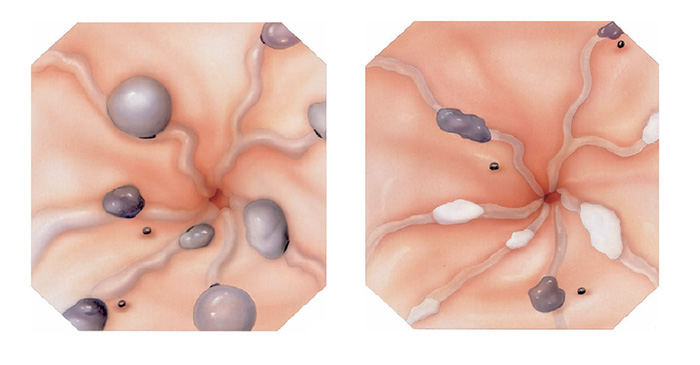

A ligadura elástica é considerado o melhor procedimento para o tratamento das varizes de esôfago. Estas surgem em pacientes que possuem pressão aumentada da veia porta (hipertensão portal) que possui várias causas sendo a principal delas a cirrose hepática.

Durante o procedimento o paciente é sedado como em toda a endoscopia digestiva. Então na ponta do aparelho é acoplado o dispositivo de ligadura elástica, ficando a manopla de disparo dos elásticos na outra extremidade do endoscópio, no local onde o endoscopista realiza as manobras com o aparelho.

Após a introdução do aparelho o endoscopista identifica as veias dilatadas (varizes) e aspira o ponto a ser ligado para dentro do dispositivo. Após isto, gira o dispositivo de ligadura soltando o anel de borracha, que estrangula a porção da variz que foi aspirada.

Este estrangulamento faz a variz diminuir de tamanho até “secar”. Este processo dura cerca de 2 semanas. As sessões são repetidas geralmente a cada 15 dias até o desaparecimento das varizes. Geralmente são necessárias de 3 a 6 sessões para o tratamento completo.

O que são pólipos?

Pólipos são crescimentos na parede interna do tubo digestivo em órgãos como o esôfago, estômago, duodeno e cólon. O cólon e o reto são partes do intestino grosso.

Por que devem ser removidos?

Se não forem removidos cedo, alguns pólipos podem se tornar cancerosos. Se pólipos cancerosos não são tratados, eles são uma ameaça à vida. Porém mesmo sendo canceroso, se for ressecado precocemente e se este não estiver muito infiltrado, a simples retirada do pólipo pode resolver o problema.

Por que apenas a biópsia de um pólipo não é suficiente?

Geralmente apenas uma região do pólipo é que se apresenta de forma cancerosa. Se for realizada uma simples biópsia do pólipo, a região cancerosa pode não ser atingida e o diagnóstico de câncer não ser realizado. Para se ter certeza do diagnóstico, o pólipo inteiro deve ser removido através do procedimento chamado de polipectomia.

O que é a polipectomia?

A polipectomia é a remoção completa de um pólipo permitindo assim o diagnóstico exato e muitas vezes a cura do próprio problema. Existem várias técnicas para a realização do procedimento que dependem do tamanho e do tipo de pólipo a ser ressecado.

Polipectomia com pinça

Pequenos pólipos podem ser removidos com segurança usando-se apenas uma pinça.

Polipectomia com alça diatérmica

Pólipos maiores necessitam ser removidos com alça e corrente de cauterização. Este procedimento permite cortar a base do pólipo e ao mesmo tempo coagular o local para evitar sangramentos.

Porém alguns pólipos possuem a base (pedículo) largo onde passam vasos calibrosos e por isto tem risco aumentado de sangramento na retirada mesmo usando a corrente de coagulação.